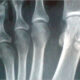

El pie es el segmento distal del miembro inferior y está diseñado para soportar el peso del cuerpo, proporcionar equilibrio y permitir la locomoción. Está compuesto por tres regiones principales: el tarso, el metatarso y las falanges. El tarso está formado por siete huesos tarsianos que se conectan con la tibia y la fíbula para formar el tobillo. Estos huesos tarsianos, como el calcáneo y el astrágalo, brindan estabilidad y amortiguación al caminar y correr. El metatarso es la región media del pie y consta de cinco huesos metatarsianos, que se conectan con los huesos del tarso y las falanges de los dedos del pie. Las falanges son los huesos de los dedos del pie, similar a los huesos de las falanges en la mano. Cada dedo del pie tiene tres falanges, excepto el dedo gordo, que tiene dos.